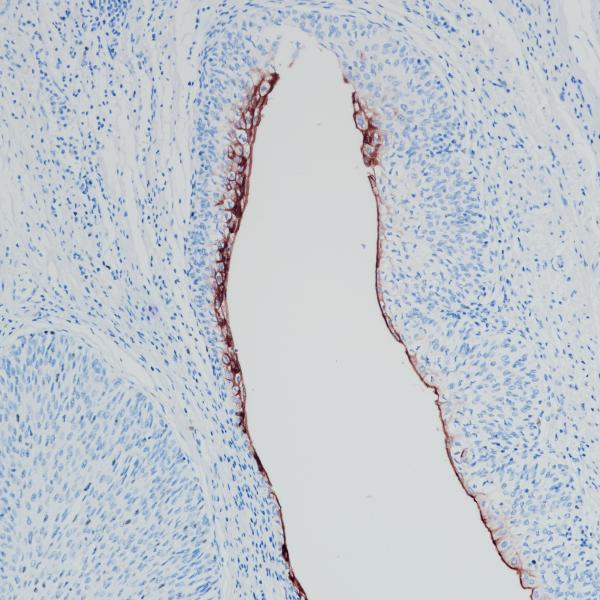

Uroplakin 1a

BP6293

Uroplakin 1b (UPK1B)

BP6310

Uroplakin II

BP6308

Uroplakin III

BP6199